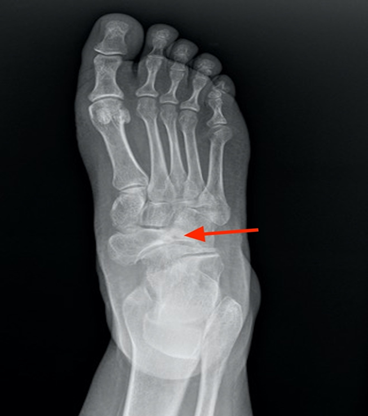

Standard x-ray is

- ankle and

hindfoot: the collapse of the lateral half of the navicular bone engenders a

medial subluxation of the talus head which provokes the hindfoot varus (figure 1).

Figure 1. Oblique radiograph of the forefoot showing the

collapse of the lateral part of the navicular bone and the medial subluxation.

(red arrow)